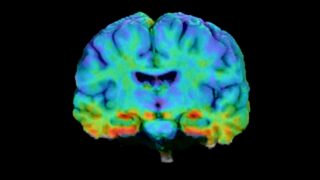

How AI and advanced computing are accelerating Alzheimer’s research

Cutting-edge technologies developed by USC researchers are changing not just the pace of Alzheimer’s disease discoveries but also the ways scientists make those discoveries.

USC study reveals differences in early Alzheimer’s brain markers across diverse populations

A USC team has identified important differences in how early Alzheimer’s-related brain changes appear across racial and ethnic groups, underscoring the need for more inclusive approaches to studying and diagnosing the disease.